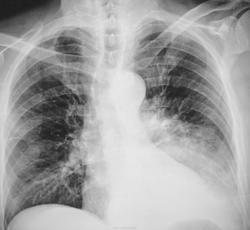

Левосторонняя нижнедолевая пневмония. лечение. динамика.

Как бы эта нижнедолевая пневмония не оказалась уже ателектазом. А почему "пневмоторакс"? Внезапные боли?

Как-то не похоже на инфильтрацию, я бы думала о гиповентиляции нижней доли и центральном образовании

Данных за пневмоторакс нет.Левосторонняя нижнедолевая пневмония(предварительно).Верхнюю долю уточнять на контроле.

Так значит ателектаз?

Я бы написала ателектаз

А не многовато ли "объема" для ателектазированной доли?

Ателектаз-гиповентиляция, суть одна. Может быть легкое еще не полностью спалось, но на пути к этому

Клиника манифестная, клиника крупозной пневмонии.

Вскрытие будет завтра. пока клинически - крупозная пневмония.

Крупозная пневмония, незначительный гидроторакс слева (со слов патологоанатома)